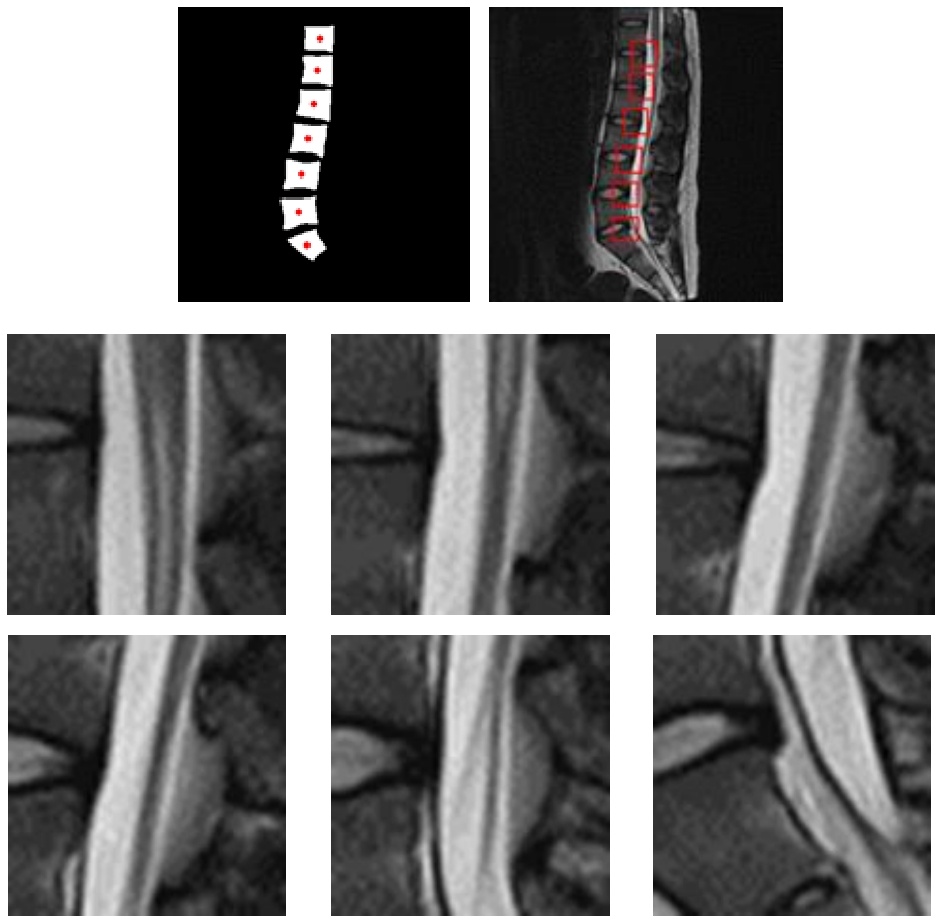

2.2 椎骨的中心定位与裁剪

对经分割处理的二值化脊柱骨骸图像中,在应用面积滤波去除一些残留的噪声后,在Python-OpenCV框架下提取出该区域的轮廓及其中心点位置(如图6所示)。随后将这些关键位置数据依次记录至txt文件中,并在后续步骤中可直接调用这些数据来实现所需区域-of-interest(ROI)的精准提取。

下载: | 高精图 | 低精图

图6 椎骨中心标记和记录

Fig. 6 Marking and recoding of vertebral center

基于获取的所有椎骨中心点坐标的定位结果,在矢状位原始图像上执行裁剪操作。裁剪区域的具体尺寸参数由经验丰富的专业医生依据腰椎间盘病灶区域(ROI)的标准尺寸来设定,并且固定为统一的48×48像素范围。具体而言,在完成所有必要的解剖学定位后,在每个目标点位置的基础上向后延伸并截取相应的等大正方形窗格进行观察分析(如图7所示)。

译

图7 ROI图像裁剪结果

Fig. 7 ROI area clipped results

下载: 原图 | 高精图 | 低精图